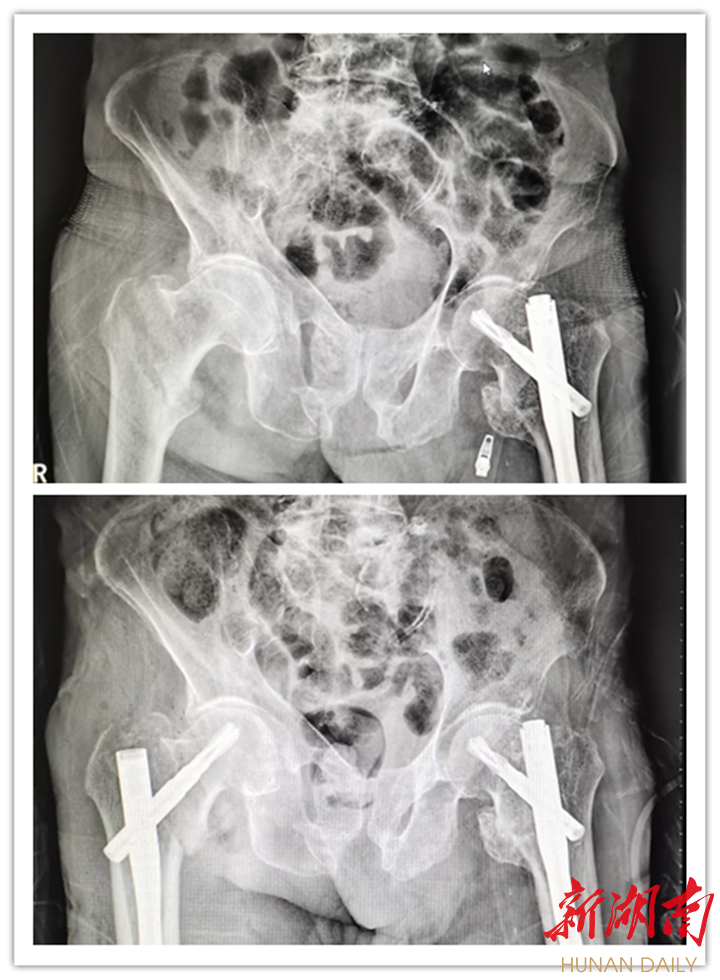

术前/术后情况

为保障手术安全和术后顺利康复,关节外科团队对邹爹爹的全身情况进行综合评估,针对麻醉方式、术中体位、手术方法等多个问题进行了全面讨论与分析。在与家属进行了充分的沟通与交流后,决定为邹爹爹实施右侧股骨粗隆间闭合复位微创固定术(PFNA),并制定了详细的个性化治疗方案。

手术如期进行。在骨外科学科主任雷青、病室主任陈松的带领下,关节外科团队仅用时20分钟便完成了手术,术中出血不足100毫升。术后邹爹爹病情稳定。不到一周,老人便在医护人员的搀扶下站了起来,迈开步子,推着助行器在病房内缓步行走。邹爹爹开心极了,向医护人员竖起了点赞的大拇指!